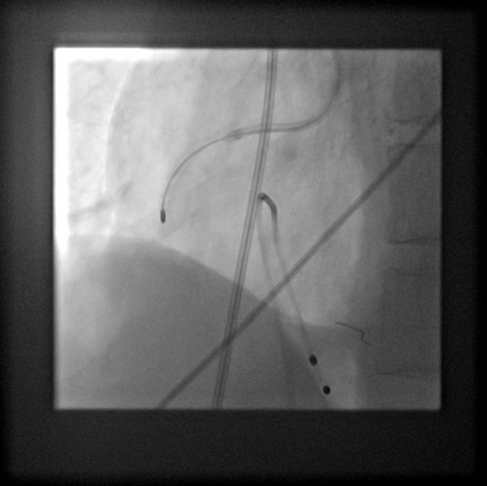

PCIof right coronary artery was initiated on IABP support with amplatz left1 guided catheter and vessel was crossed with great difficulty in repeatedattempts by fielder XT followed by GAIA 2 wire over corsair microcatheter. Microcathetercould not be crossed beyond mid segment calcified CTO, so balloon dilation with0.75 mm balloon was done after which again microcatheter could not be trackedbeyond mid part. Butwe were able to exchange wire to allstar followed by rotawire byplacing microcatheter in mid segment after balloon dilation by 0.75 mm balloon. Rotablation wasdone with 1.25 mm burr at 1,60,00 rpm repeatedly from proximal to mid distalpart. Lesionstill looked unprepared as repeated postdilation with2.25*15 mm followed by 2.5*15 mm non compliant balloon at high pressures showedunexpanded balloon. Againlesion preparation was done with 2.5*15 mm wolverine cutting balloon repeatedlyat high pressures which led to adequate luminal gain and calcium cracks as seenon IVUS run. AfterIVUS run again high pressure balloon dilation was done with wolverine 2.5*15 mmballoon followed by 2.5*12 mm non compliant balloon at 28 atm toadequately prepare the lesion before stent deployment. Stentingwas done with 2.5*32 mm DES, 2.75*32 mm DES, and 3*24 mm DES from distal toproximal in overlapping fashion. Thenfinally high pressure post dilation was done with 2.75*15 mm followed by 3*15mm non compliant balloon and adequate stent expansion was achieved with TIMI 3 flow.